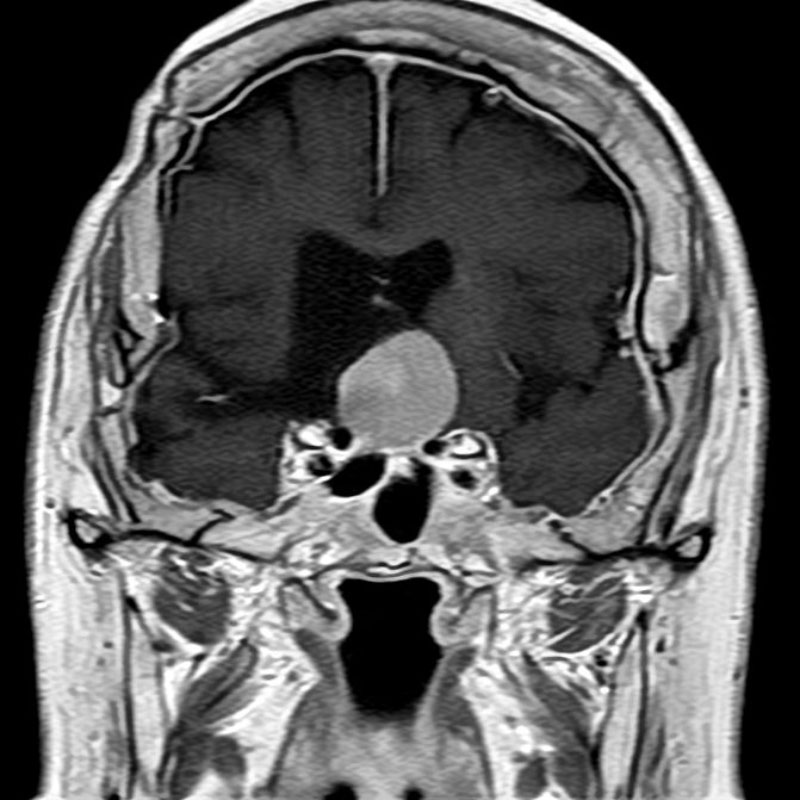

493

'23年12月

40代

頭蓋咽頭腫

頭蓋内腫瘍摘出術

No.’23_127 手術前1

No.’23_127 手術前2